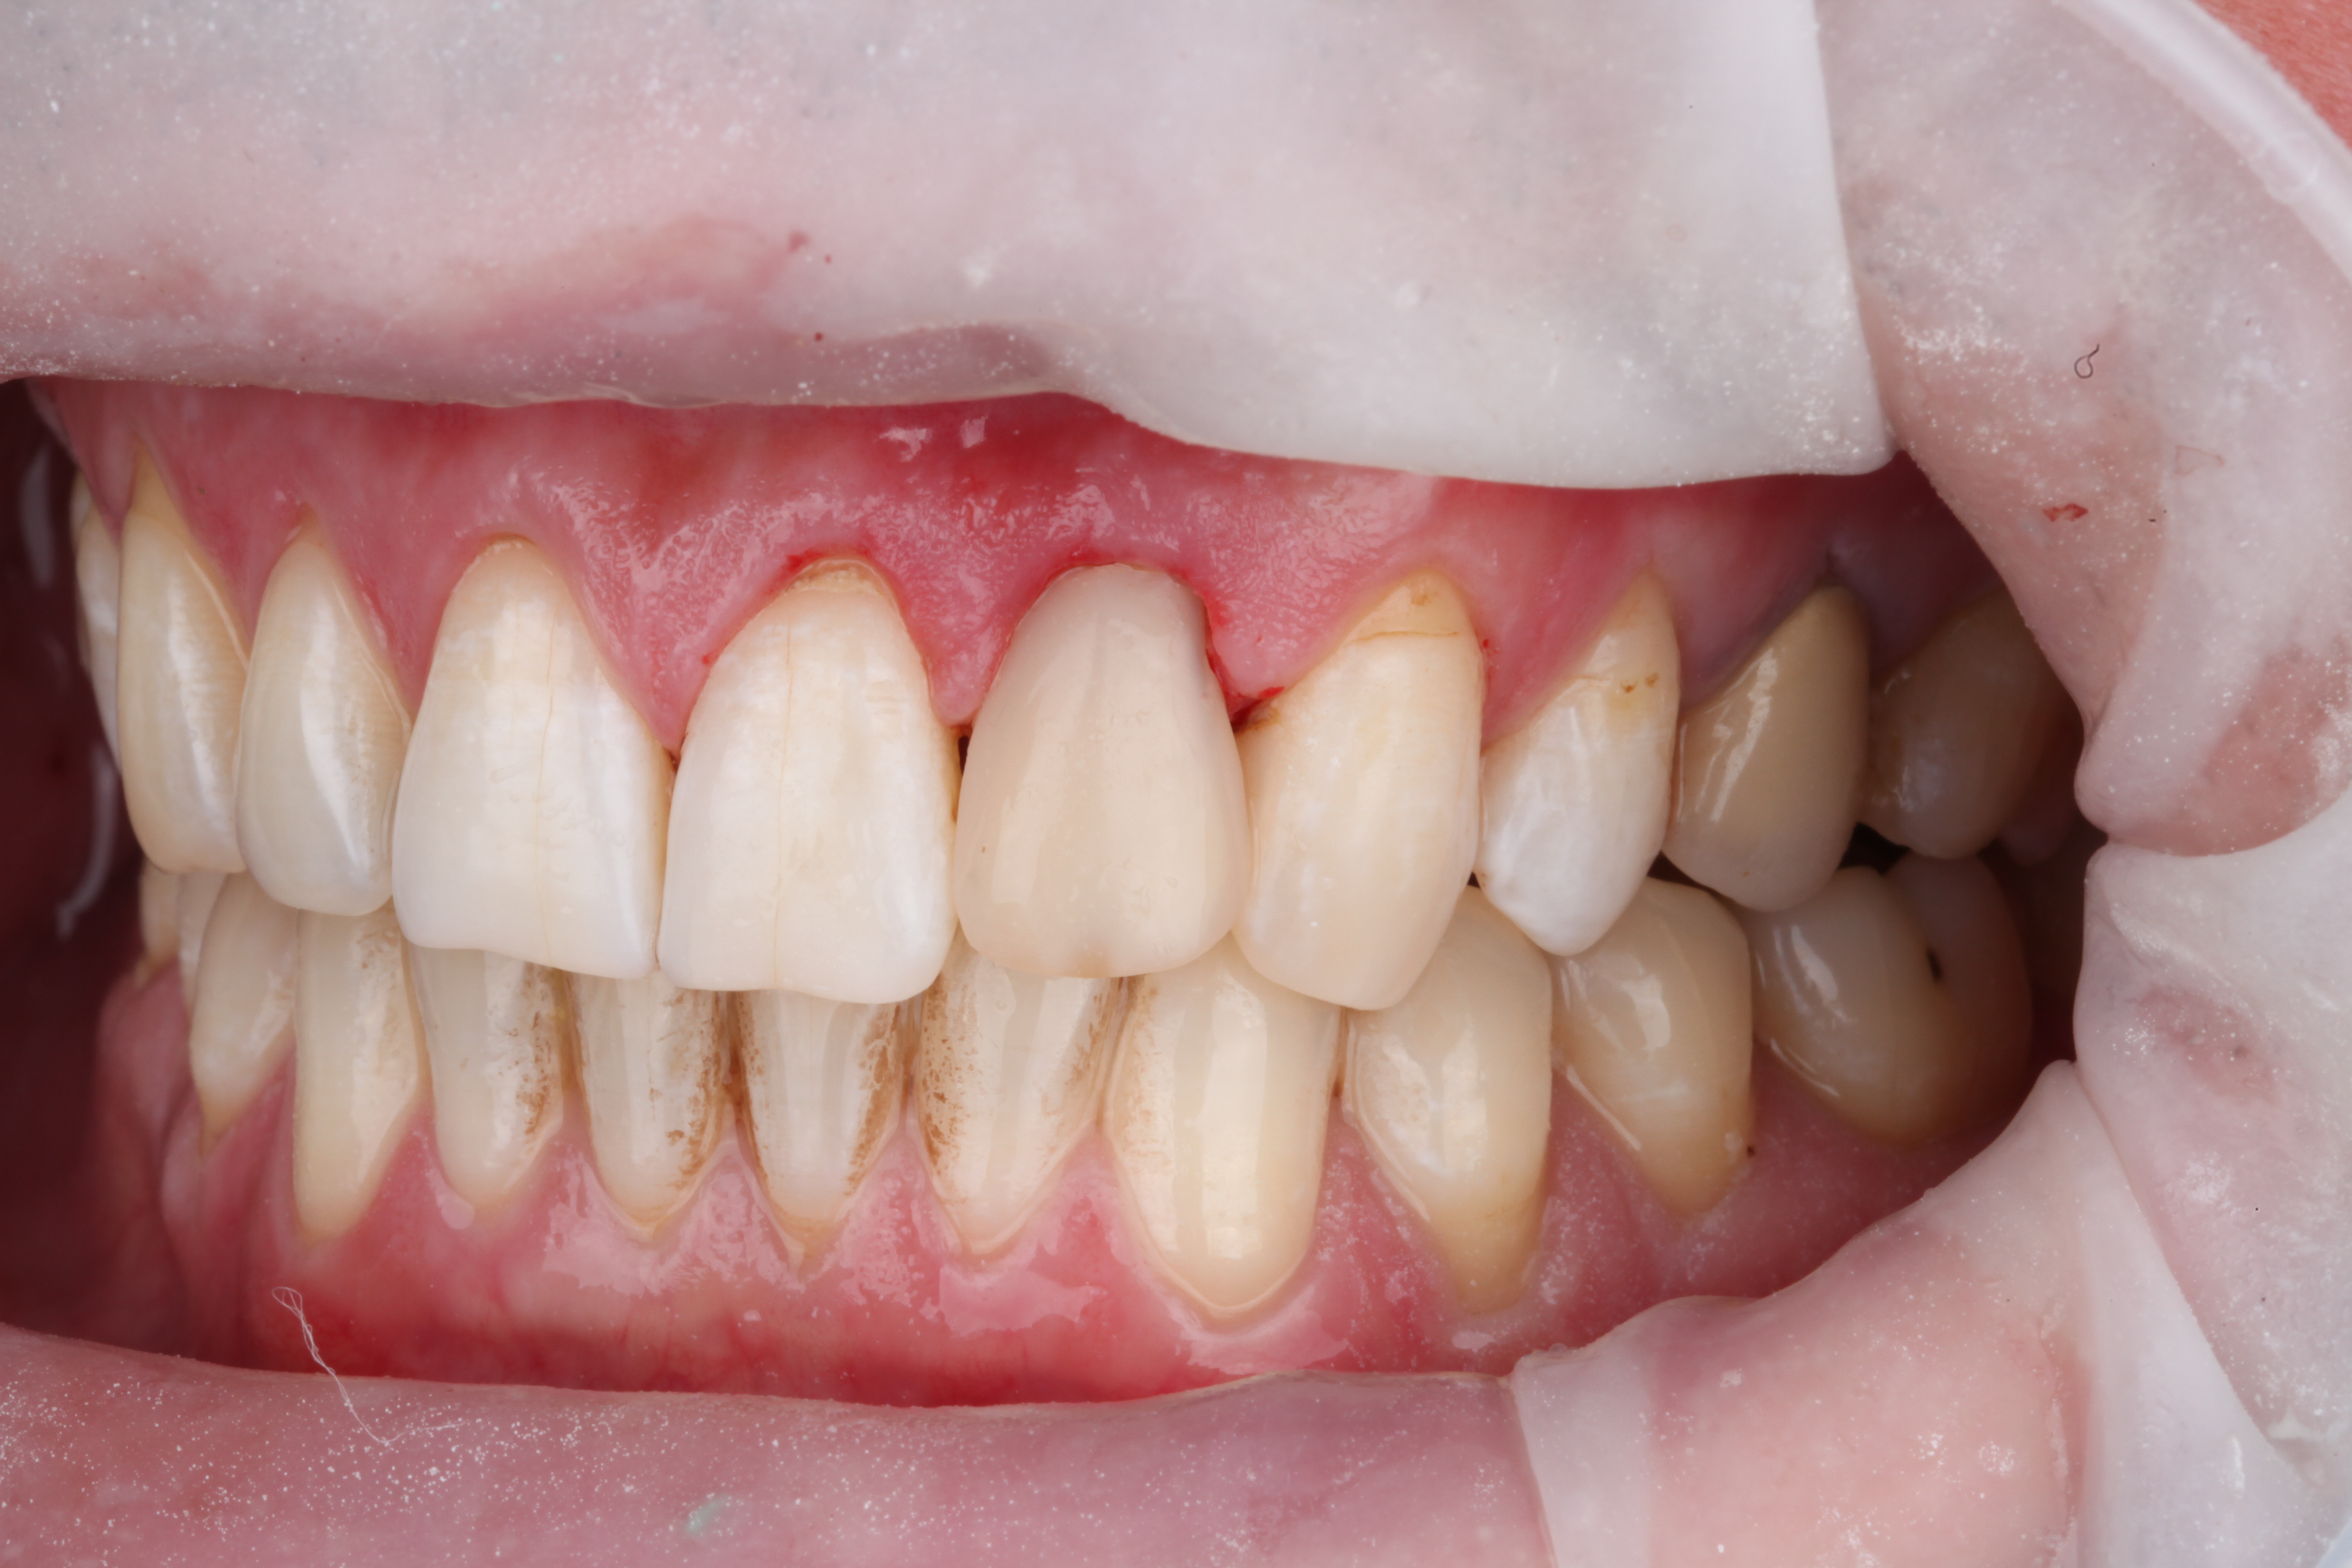

Клиническая картина с которой пациент обратился к нам:

Исходная клиническая ситуация